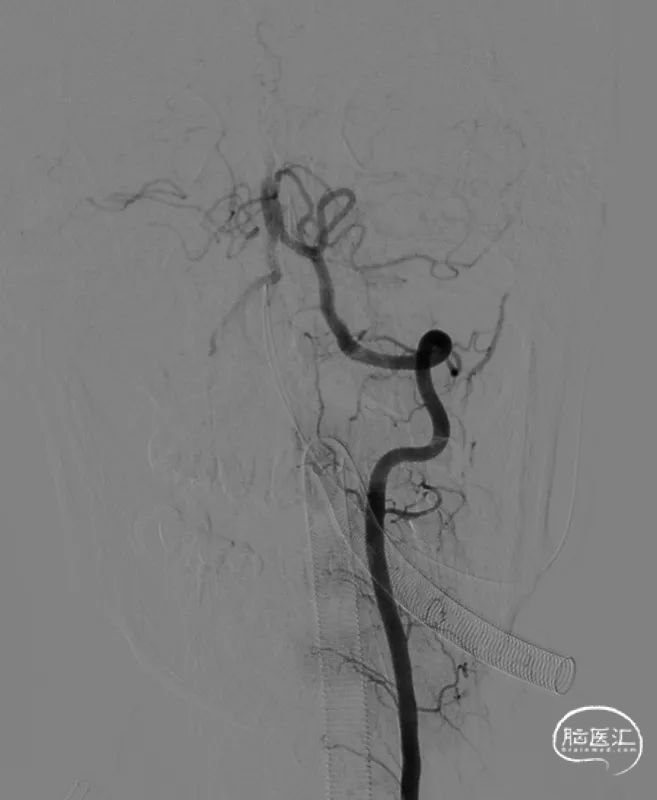

左侧椎动脉造影。

6F 125cm 通桥银蛇®颅内支持导管到位。

负压抽吸2次,基底动脉顶端部分再通,见栓子向双侧大脑后动脉逃逸。